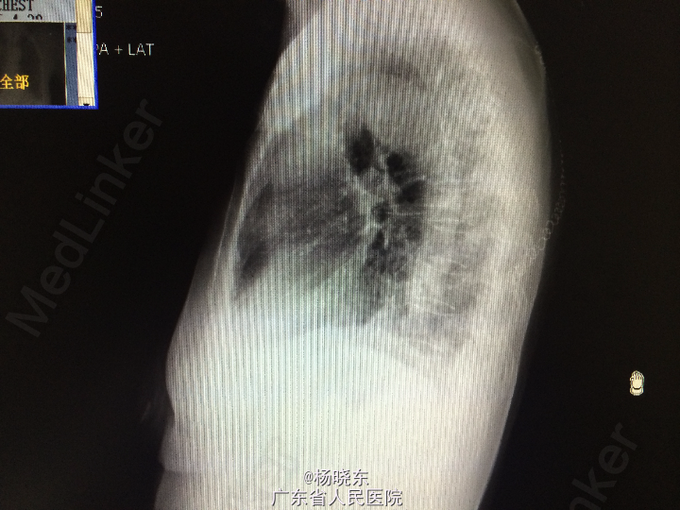

主诉:反复胸背痛1年,加重1月。 病史:患者1年前无明显诱因出现右侧胸背痛,性质为隐痛,无向周围放射。遂至当地医院门诊就诊,查胸部CT,考虑“胸膜肿瘤”,建议手术处理,但患者拒绝未予治疗,症状持续数天后自行消失。后间断出现类似症状,但均可忍耐。1月前患者自觉右上肢上抬及抬举重物时右侧胸背痛明显,不伴有其余部位牵涉痛,未予重视。近1周来,患者自觉症状加重,疼痛致右上肢不可上抬,弯腰时加重,平卧时可缓解。现为进一步手术治疗入院,无发热,无头晕、头痛,无咳嗽、咳痰,无气促、心悸,无恶心、呕吐,无腹痛、腹泻,无皮疹、无双下肢浮肿。自起病以来,精神、睡眠可,食欲可,二便正常,体重近1月下降2kg。

查体:右侧胸肋部及肩胛区压痛明显。 辅查:胸片,CT。

诊断:胸膜间皮瘤 处理:右侧胸膜肿瘤切除术

术中病理显示为结核脓肿,改行右侧胸膜结核性脓肿扩大清除术+右肺楔形切除术。 术后予加用异烟肼+利福平+乙胺丁醇联合抗结核治疗。